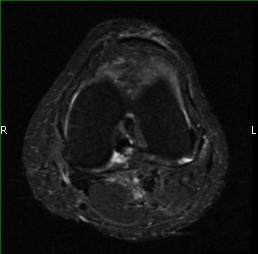

MRI (Fig. 1-10)

- Periarticular or synovial nodular mass with varying degrees of bone erosion.

- Nodular lesion with areas of hemosiderin (low signal on all sequences) and hemorrhage.

- On fat suppress images the tumor is high signal and hemosiderine cannot be seen.

- Joint effusions and bony erosions are well demonstrated. As with CT, contrast enhancement is typical.

Fig. 1-10: Magnetic Resonance of a PVNS of the knee shows a synovial mass with minimal bone erosion of the medial articular plate. On T1W and T2W images shows a tumor with low intensity areas (hemosiderin) and hemorrhage. Joint effusion is well demonstrated. Post contrast images demonstrate an irregular pattern of enhancement.